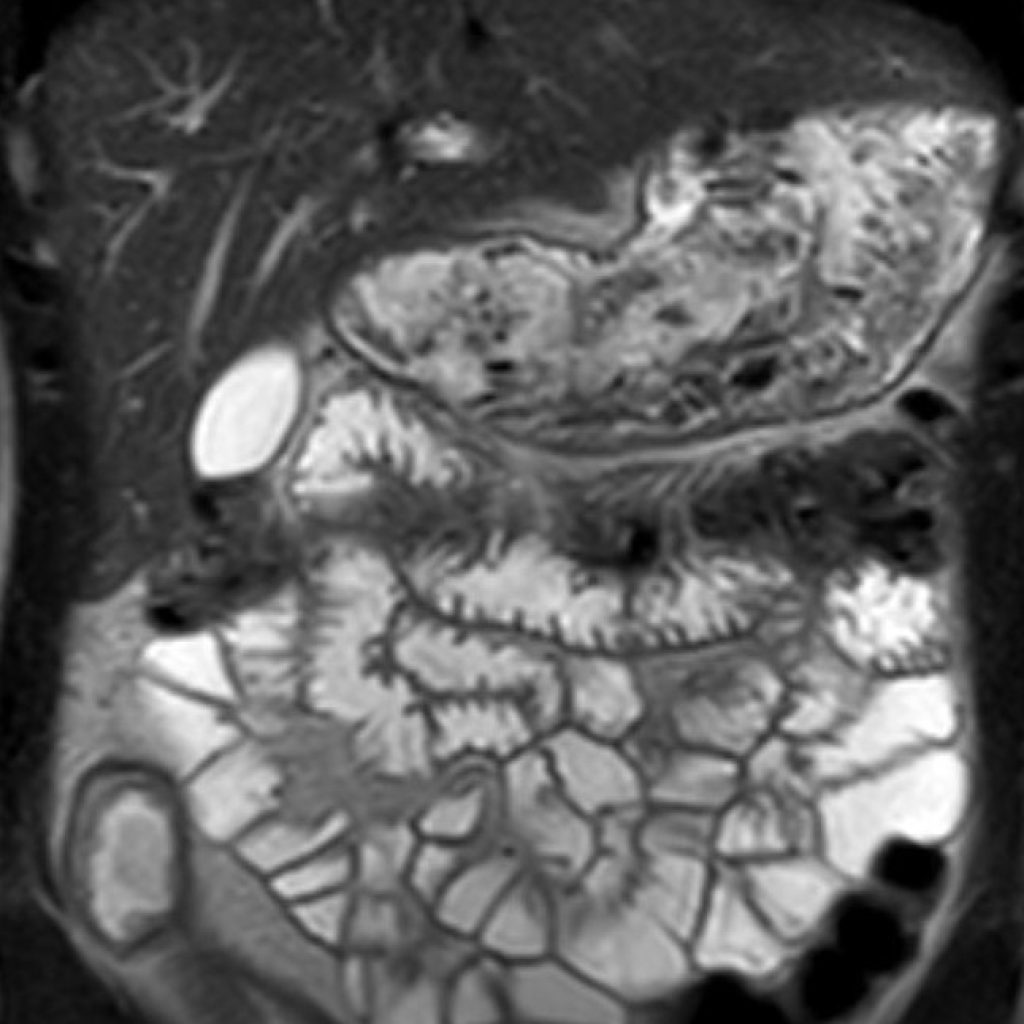

L’IRM abdominale est d’une grande utilité lorsqu’une analyse très fine des organes situés au sein de la cavité abdominale est nécessaire et que certaines lésions ne sont pas visibles avec les autres techniques d’imagerie (radiographie, échographie ou scanner).

Elle permet de réaliser des images en coupe ou acquisitions 3D apportant non seulement des informations sur l’anatomie de l’organe mais également sur la viabilité de certaines lésions et d’évaluer ainsi la réponse au traitement de façon plus précise.

Ce type d’exploration s’intéresse au foie, aux surrénales, aux reins, au pancréas, à la rate et au péritoine

Quelques exemples :

– recherche d’une surcharge en fer du foie,

– quantification d’une stéatose, suivi des fibroses intra-hépatiques,

– cartographie des lésions cancéreuses et suivi de leur réponse sous traitement,

– recherche de calculs au sein des voies biliaires ou de la vésicule.